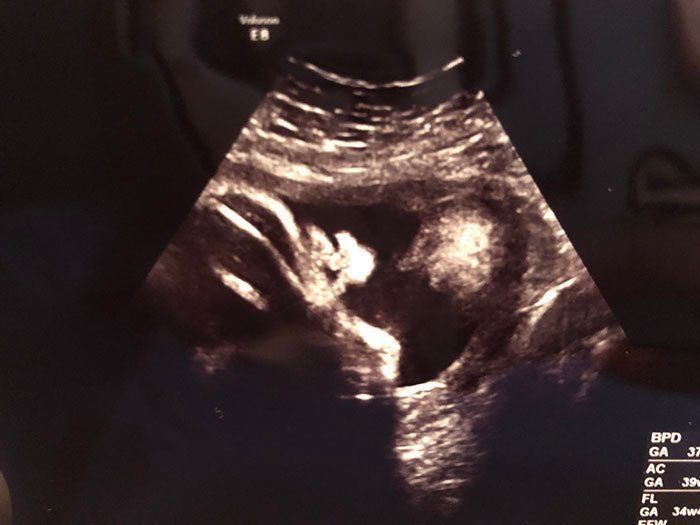

妊娠21週目 つわりからの解放、食欲が少しずつ戻る

妊娠21週目のエコー写真です。すでにつわりが落ち着き、食欲も出てきた頃で、マタニティマークをつけていなくてもバスの席を譲ってもらえるほど、おなかが目立ってきていました。そのせいもあるのか、この時期は腰痛になってしまい、骨盤ベルトを常に締めて過ごしていました。